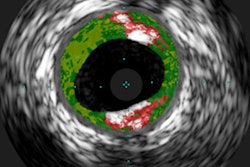

Trump's official medical records disclosed a coronary artery calcium score of 34 in 2009; the score surged to 98 in 2013 and has now reached 133 -- far exceeding the minimum score of 100 required to confirm the presence of calcium plaques, according to an article by CNN Chief Medical Correspondent Dr. Sanjay Gupta.

The president's CAC score places him in the midrisk range, or 46th percentile, for heart disease, and his level of plaque is "common" for someone of his gender, race, and age. The condition is "relatively easy to address" if Trump increases the dose of his cholesterol-lowering medication and makes lifestyle changes, according to Gupta.